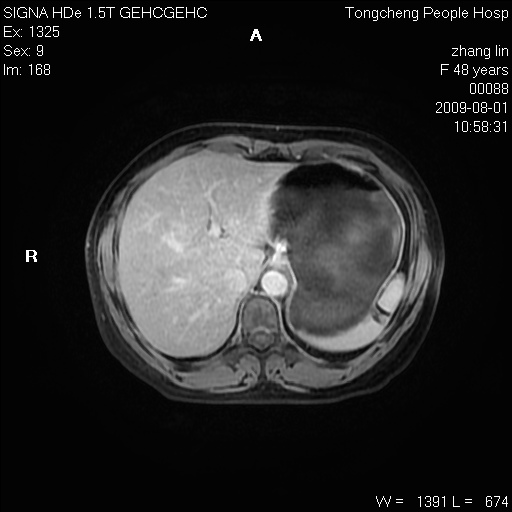

女,48岁。健康体检,彩超发现右肾占位性病变。平素健康。

临床诊断:右肾占位性病变,性质待定(囊肿?肿瘤?)。

上中腹部mr平扫+增强扫描,图像如下:

右肾上极见一类圆形病灶,t1wi呈等信号t2wi呈等高混杂信号,三期增强无强化,边界清---考虑囊肿出血。

肝囊肿